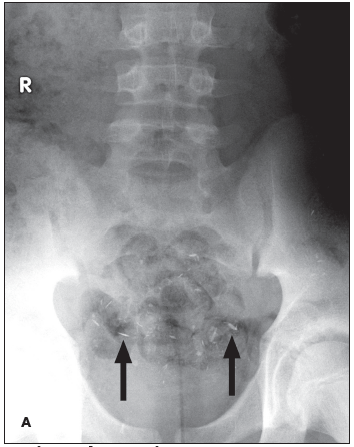

This 12-year-old girl had a persistent, nontender enlarged lymph node in the right groin.

Melissa R. Larzo, MD; Linda S. Nield, MD; Deepak M. Kamat, MD, PhD

The authors review the types of fractures that are possible in an accidental fall, depict the most common mechanism of fracture, and provide recommendations about when child protective services should be...